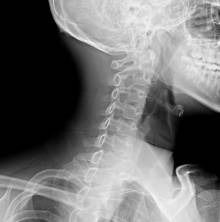

Шейный остеохондроз – дегенеративно-дистрофическое заболевание, поражающее хрящевую ткань межпозвоночных дисков. Оно может возникнуть и в очень молодом возрасте, до 30 лет. Шейный остеохондроз проявляется резкими болями в шее, давящей головной болью, отдающей в виски, иногда наблюдается ухудшение зрения, головокружения и боли в области сердца, напоминающие стенокардию.

Когда такая ситуация повторяется регулярно, то начинает интересовать вопрос, можно ли предотвратить боль в шее и в чем истинные её причины? Почему возникает боль в шее справа или слева, или только при повороте головы, а в некоторых ситуациях отдает в голову (затылок, виски), болят плечи или боль распространяется на спину? Множество вопросов объединяет заболевание остеохондроз, при котором стареющий позвоночник теряет свои свойства: нет былой упругости дисков, деформируются тела позвонков.

- межпозвоночная грыжа шейного отдела позвоночника;

- протрузия диска;